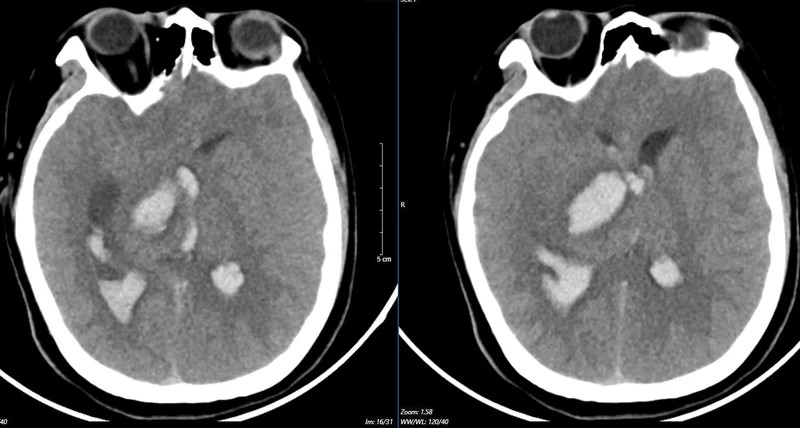

| |

Hình ảnh chụp MSCT mạch não: Chảy máu não thuỳ đỉnh phải, chảy máu não thất do vỡ AVM ( điểm Spetzler Martin 2 điểm) của bệnh nhân nữ, 29 tuổi. |

Nữ bệnh nhân 29 tuổi, tiền sử khoẻ mạnh. Bệnh nhân đến viện vì đột ngột đau đầu, tê tay, nôn nhiều vật vã. Tại bệnh viện tỉnh, bệnh nhân được chẩn đoán chảy máu não, các bác sĩ đã đặt ống nội khí quản thở máy rồi chuyển tuyến lên Trung tâm Đột quỵ, Bệnh viện Bạch Mai trong tình trạng ý thức hôn mê, Glasgow 6 điểm, thở máy, đồng tử bên phải giãn 4mm, tụt huyết áp, duy trì vận mạch.

Kết quả chụp MSCT mạch não cho thấy chảy máu não thuỳ đỉnh phải, chảy máu não thất do vỡ AVM ( điểm Spetzler Martin 2 điểm). Bệnh nhân đã được phẫu thuật lấy máu tụ và khối dị dạng. Tuy được điều trị tích cực nhưng di chứng để lại vô cùng nặng nề. Sau một tháng điều trị, bệnh nhân chưa nhận thức được, liệt hoàn toàn nửa người trái…